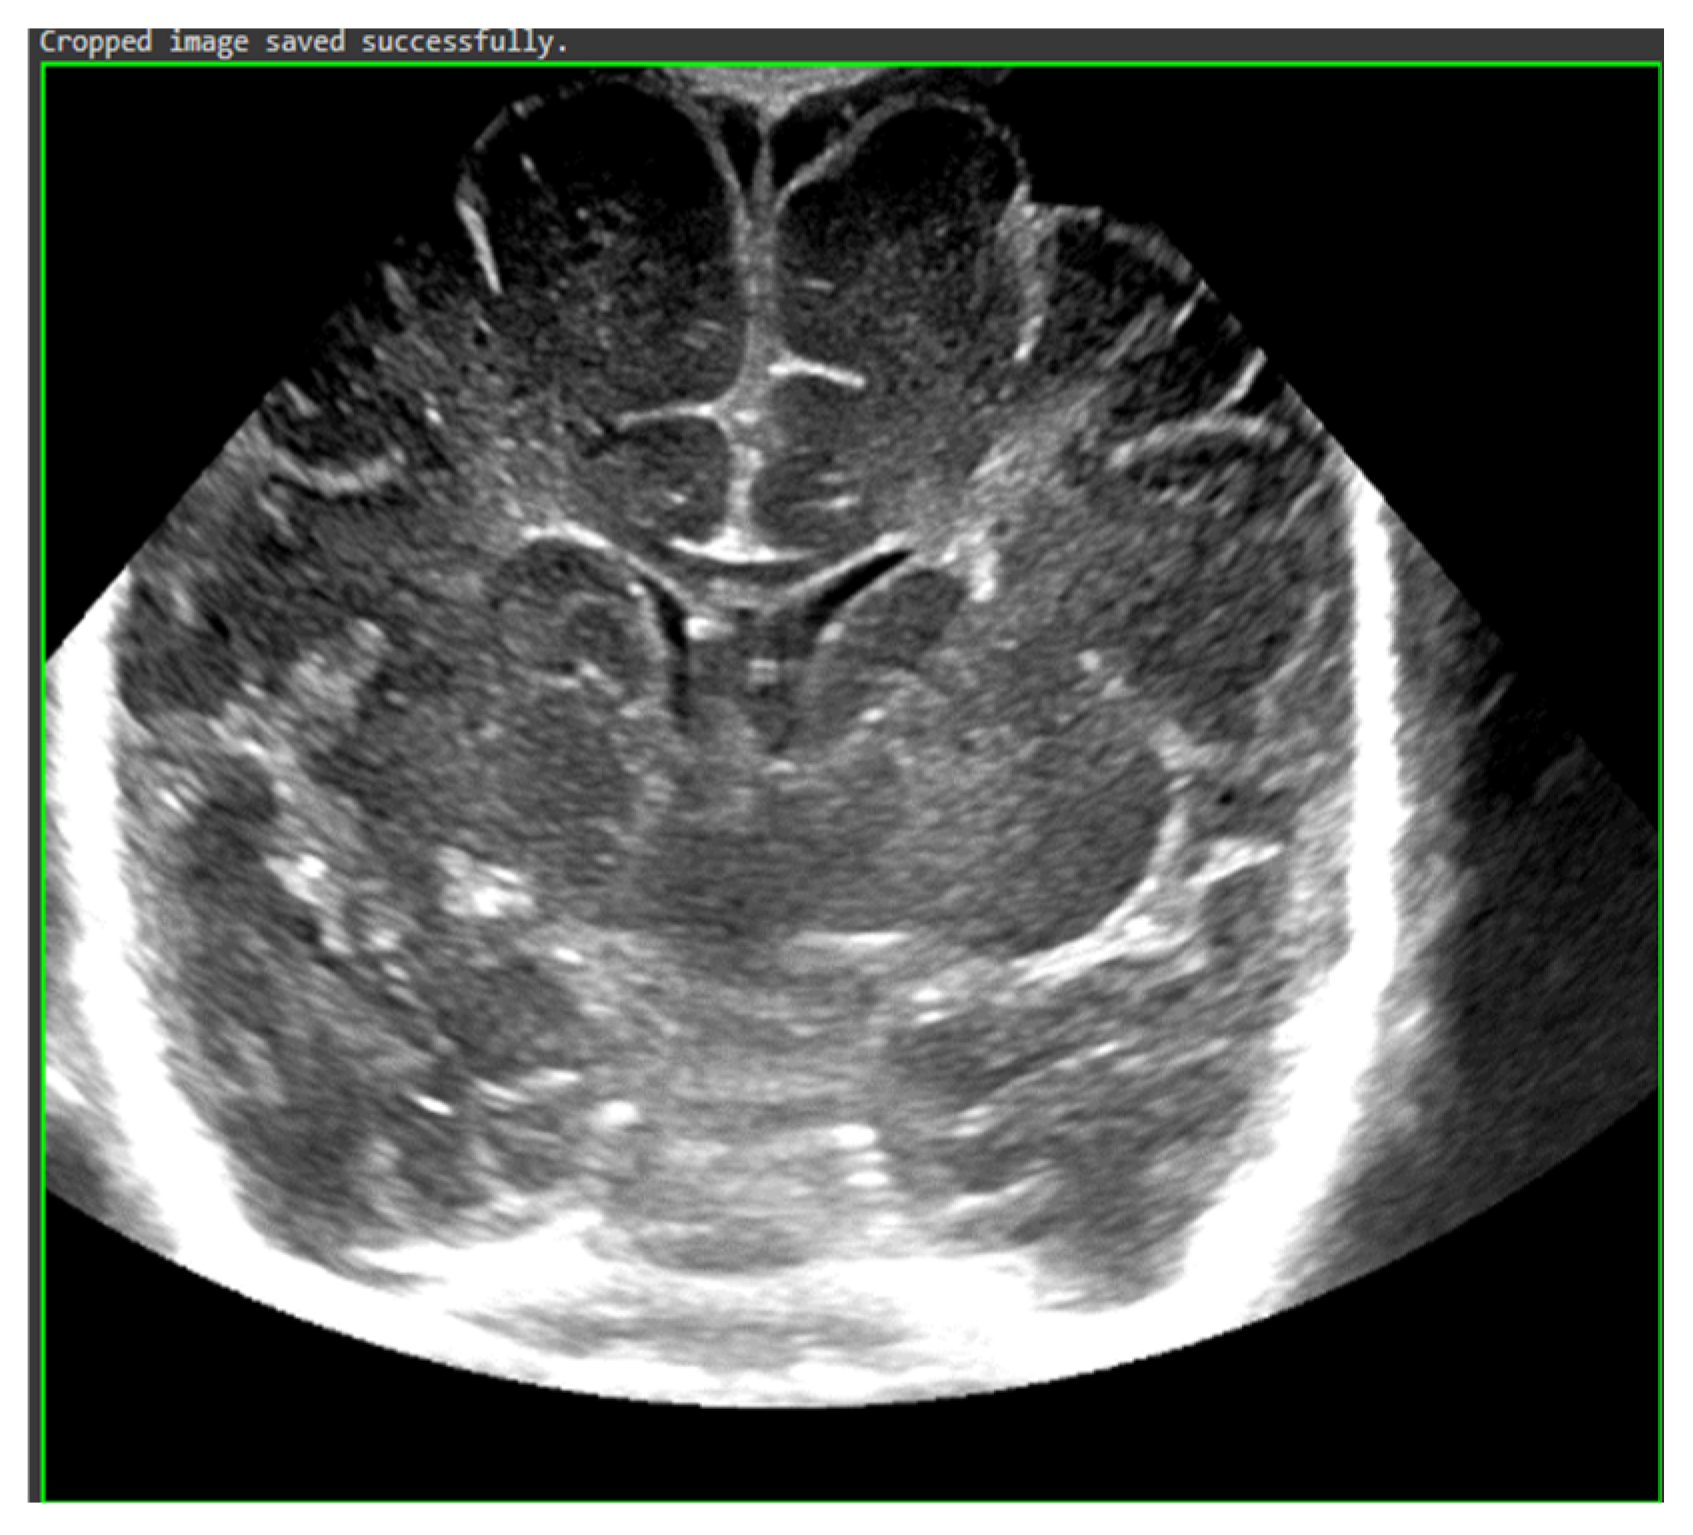

The study population comprised neonates who underwent cranial ultrasound (US) at King Fahad Hospital of the University (KFUH) in Khobar, Kingdom of Saudi Arabia. Neonatal cerebral ultrasound images were collected for this study. The inclusion criteria encompassed neonates who had undergone cranial US at KFUH, with complete sets of left sagittal, right sagittal, and coronal cranial ultrasound images, and those with confirmed diagnoses of germinal matrix hemorrhage (GMH), as shown in Figure 2. Exclusion criteria included neonates without complete sets of the required cranial US images and patients with incomplete or missing medical records. The study initially considered a total of 582 neonates who underwent cranial US, among whom approximately 40 were identified to have GMH.

Figure 2.

Sample of the dataset ((left): coronal US, (right): left US).